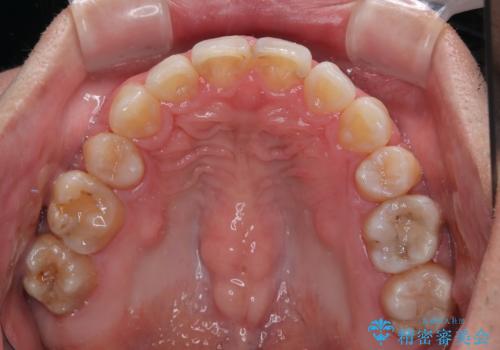

顎が左右にずれた咬み合わせ ハーフリンガルの抜歯矯正

それでも想定以上に治療期間は長期化せず、咬み合わせも口元も満足のいく仕上がりとなりました。